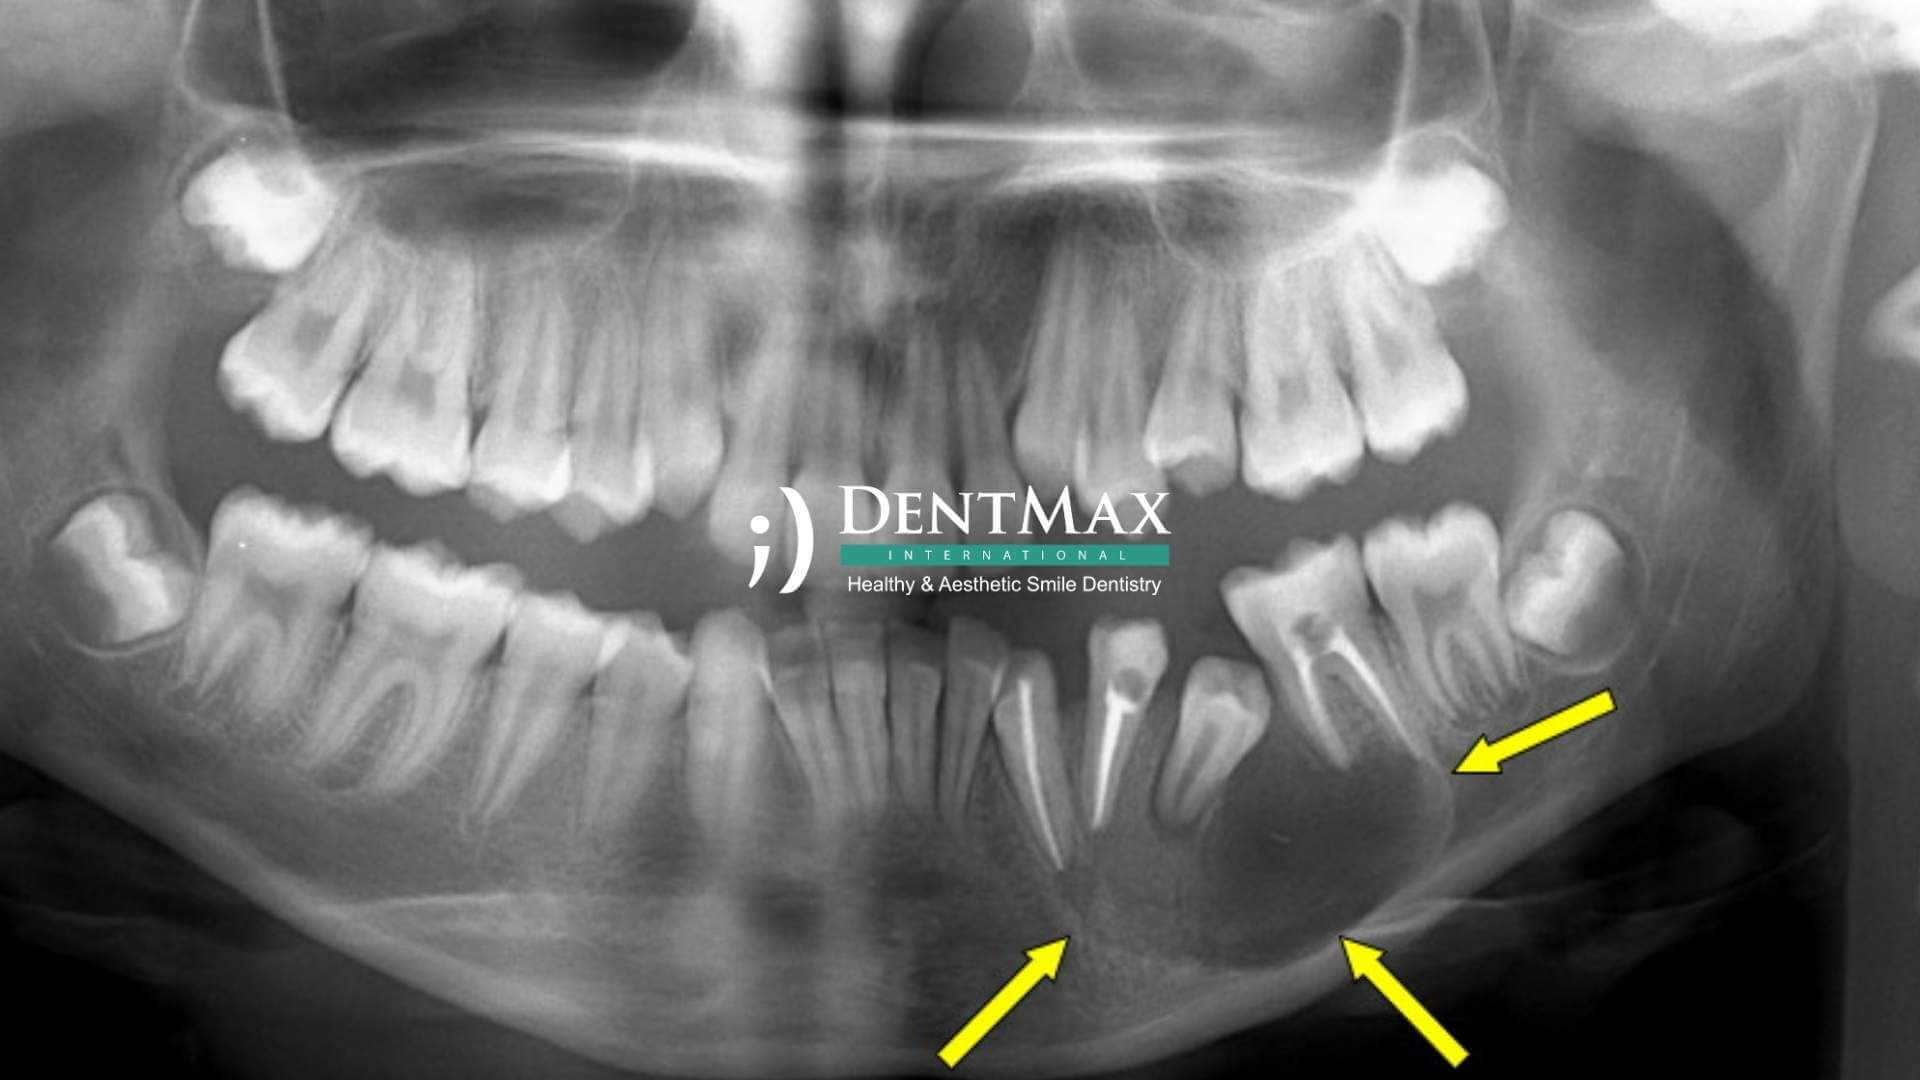

Çene kisti, genellikle enfeksiyon, gömülü dişler veya travma nedeniyle çene kemiği içinde sıvı dolu boşluklar şeklinde oluşan patolojik yapılardır. Belirtileri arasında ağrı, şişlik, dişlerde gevşeme veya çene kemiğinde incelme görülebilir. Erken teşhis, diş ve çene yapısının korunması açısından büyük önem taşır.

1. Aşama – Teşhis ve Görüntüleme

Öncelikle dental tomografi (CBCT) çekilerek kistin boyutu, konumu ve çevre dokularla ilişkisi değerlendirilir.

Panoramik röntgen ve klinik muayene sonucunda kistin türü belirlenir.

Dental tomografi (CBCT), panoramik röntgen ve gerektiğinde iMetric 4D ölçüm sistemi kullanılır.